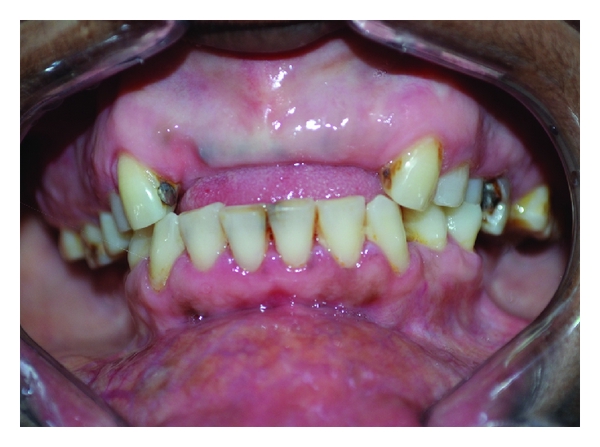

Clinical examination revealed diffuse, firm gingival enlargements symmetrically involving the maxillary and mandibular gingiva bilaterally (Figure 1). The enlargements were more severe in the molar region (Figure 2) and crowns were covered by soft tissue (Figure 3). Her family members were requested to report for clinical examination. Her elder sister was 25 years of age. She also had bilateral, symmetrical, and gingival enlargements in the posterior region of maxillary and mandibular gingiva (Figure 4). The teeth were displaced from their normal position. She also had retained deciduous teeth and multiple grossly decayed teeth (Figure 5). Her elder brother was 35 years of age. He also had bilateral, symmetrical enlargements, more prominent in the molar region (Figure 6). He also had severe malocclusion with arch collapse (Figures 7 and 8). Her mother was 62 years of age. She gave a history of similar enlargements in her gingiva and underwent multiple gingival surgeries for the same reason. Clinical examination revealed multiple missing teeth and remaining roots (Figure 9), and gingival enlargement was still evident in the molar region of mandible (Figure 10).